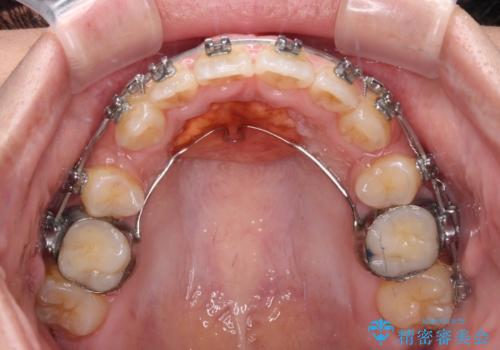

- メタルブラケット

- 3年3ヶ月

- 30回以上